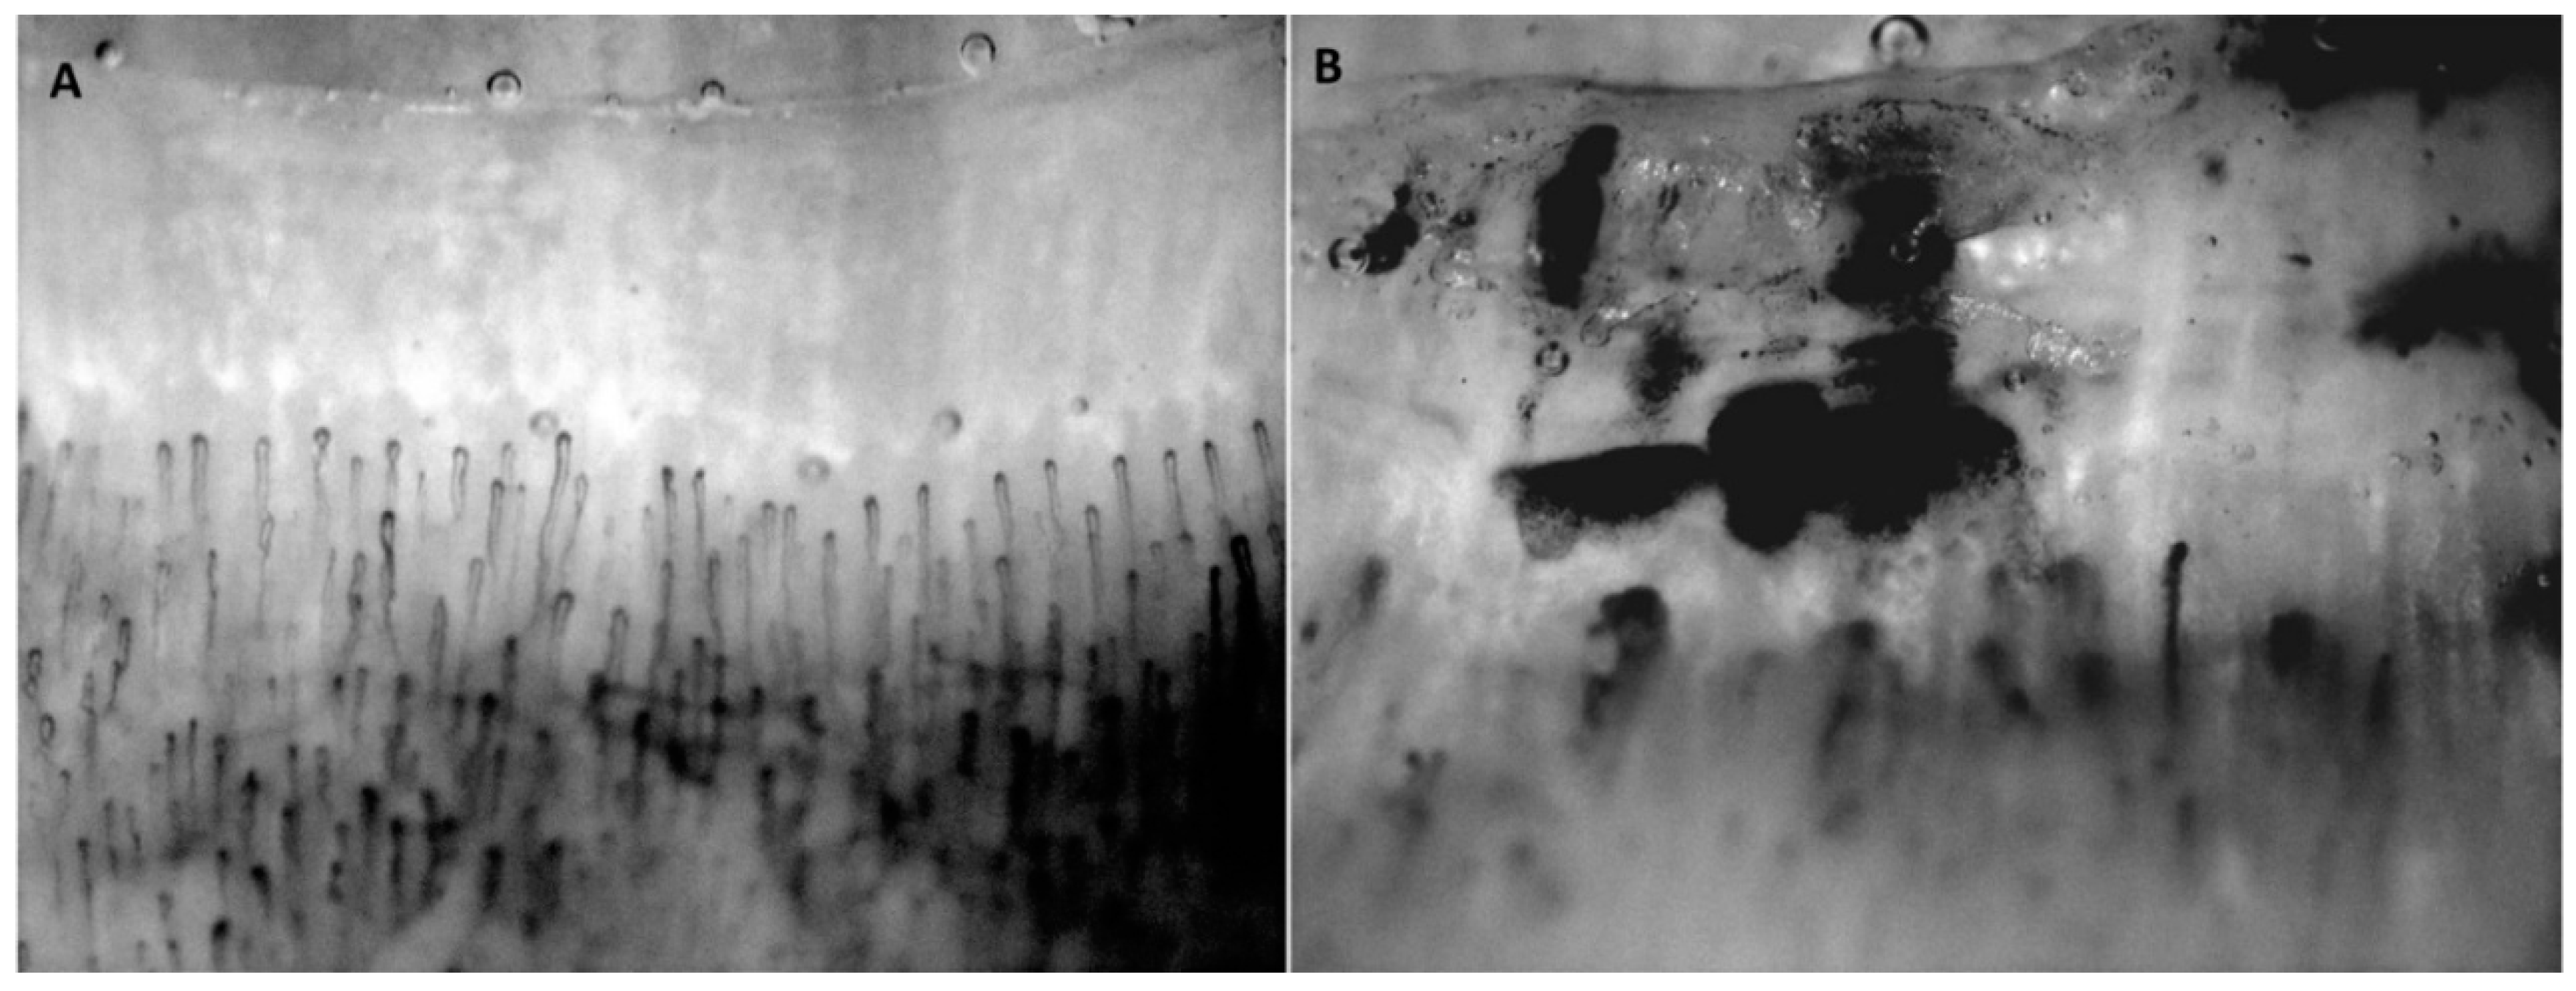

Figure 3.

Nail-fold capillaroscopy patterns of a healthy subject (A) and a subject with systemic sclerosis (SSc) (B). The images of the nailfolds were taken at 180× magnification.